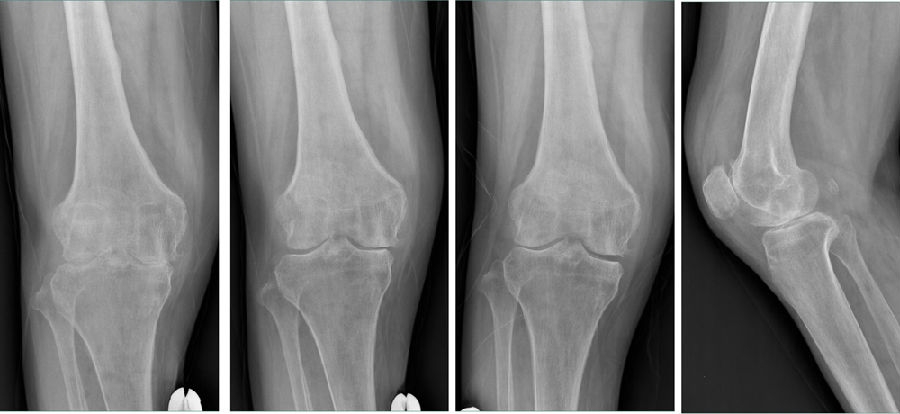

Case2:二期Bi-UKA治疗进展性OA

术前影像

术后5年,外侧进展性OA

LUKA治疗外侧进展性OA